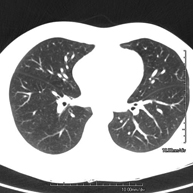

- TC Tórax

Prueba diagnóstica que consiste en obtener imágenes del tórax de alta definición anatómica (pulmones, corazón, mediastino, grandes vasos, caja torácica, etc.) mediante el empleo de un equipo de TC (Tomografía Computarizada). Dichas imágenes se estudian posteriormente en una estación de trabajo que permite reconstrucciones bidimendionales en diferentes planos del espacio y también reconstrucciones 3D (volumétricas). Algunos estudios requieren el empleo de contraste yodado para mejorar la definición de las imágenes. - Angio-TC Aorta torácica

Prova diagnòstica que consisteix en l'estudi del pulmó mitjançant l'ús d'un equip de TC (Tomografia Computeritzada) per obtenir imatges bi i tridimensional que permeten un estudi anatòmic altament específic del pulmó per poder valorar les estructures anatòmiques de petites dimensions. És una tècnica molt important en l'estudi dels pacients amb sospita de malaltia pulmonar. - TC d'estern